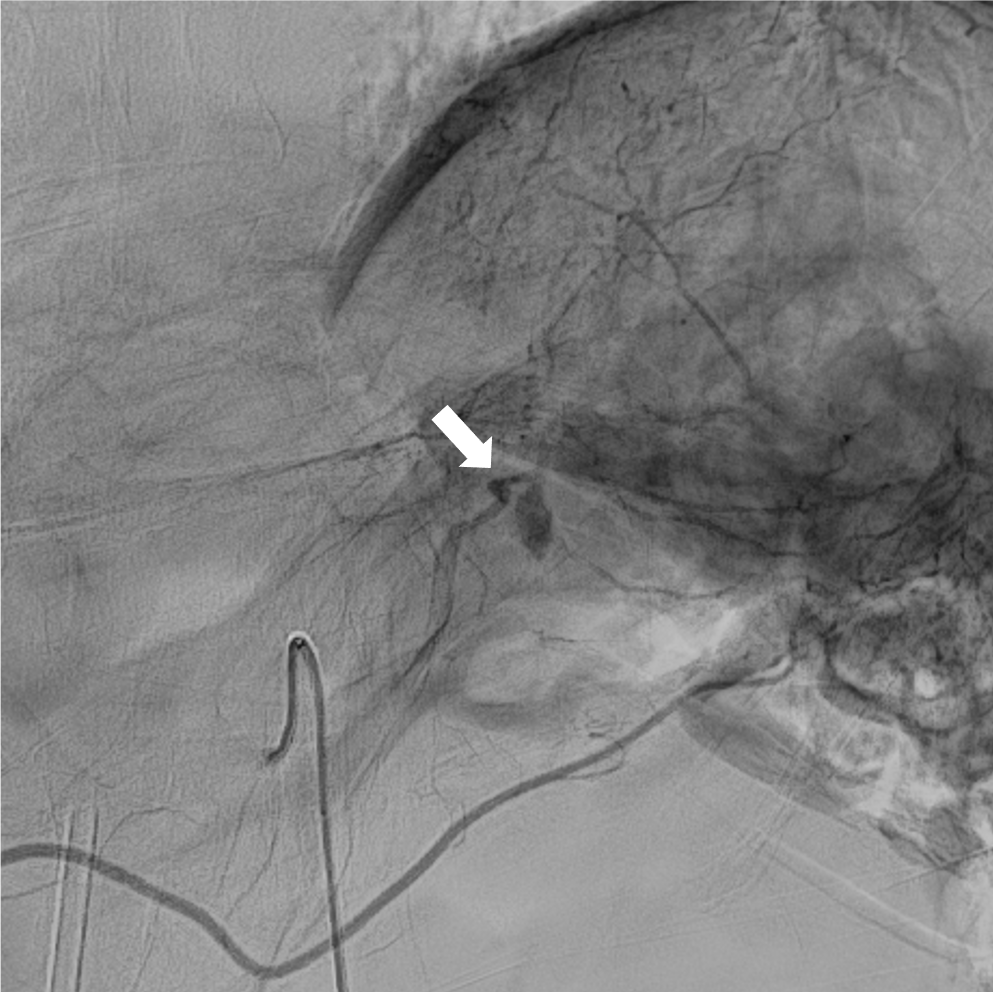

検診で指摘された肺病変のCT精査にて、肺の動静脈奇形(AVM)と診断された。精査および加療目的で当院に紹介され、術前精査のための造影CTを施行した。造影CTにて、膵尾部にAVMを認めた。その後、肺AVMに対するコイル塞栓術が施行され、その際に膵AVMも血管造影にて精査が行われた。膵AVMによる症状はなく経過観察とされ、外来にて定期的にフォローアップされている。

オスラー病(遺伝性出血性毛細血管拡張症、HHT)は、全身の血管に異常を生じる、常染色体優性遺伝の遺伝性疾患であり、特に肺・脳・肝臓・消化管などの動静脈奇形(AVM)や、鼻出血、口・指・鼻などの毛細血管拡張を生じることで知られる。膵臓にも30-60%の患者に血管病変を生じるとされ、その約2/3が毛細血管拡張、約1/3がAVMと言われている。

単純CTでは膵臓の異常血管の描出は困難であり、造影CTは診断において重要である。膵臓のAVMにおいては、(1)拡張・蛇行した供血路、排血路といった異常血管の描出や、(2)動脈相で門脈系の血管の早期造影効果が認められ、診断のポイントとなる。造影CTは血管造影と比較して侵襲性が低く、膵実質の全体の評価にも適しているため、精査のみならず、フォローアップにも用いやすい。